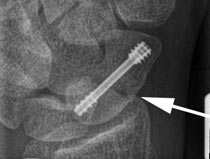

Da sich bei konservativer Behandlung im Durchschnitt etwa bei 15 % der Fälle eine so genannte Falschgelenkbildung (Pseudoarthrose) entwickelt, sollten instabile Brüche und verschobene Brüche besser operativ versorgt werden. Weil der Knochen etwa zu 85 % von Knorpel umgeben ist, sind normale Schrauben nicht geeignet, da sie zu Gelenkirritationen führen würden. Es wurde deshalb von dem australischen Handchirurgen Timothy Herbert eine spezielle Schraube entwickelt, die statt des Schraubenkopfes einen zweiten etwas breiteren Gewindeanteil besitzt. Beide Gewinde haben unterschiedliche Steigungen. Deshalb bewegen sich die Bruchenden beim Einbringen der Schraube aufeinander zu und es entsteht eine gute Kompression und sichere Fixierung.

Eine wesentliche Neuentwicklung war die Verwendung einer durchbohrten Schraube.Bei der Operation wird zunächst ein Führungsdraht eingebracht. Nachdem der Draht röntgenologisch sicher an der korrekten Stelle platziert ist, wird darüber die Schraube, die im Zentrum hohl ist, eingebracht. Dadurch sind Fehllagen der Schraube durch sekundäre Dislokation nahezu ausgeschlossen, sofern der Führungsdraht korrekt eingebracht wurde.

Solche Schrauben wurden zum Beispiel von der Firma Martin in Form der HBS-Schraube (Headless Bone Screw) oder von der Firma Stryker mit der Twinfix-Schraube entwickelt. Inzwischen gibt es aber von weiteren zahlreichen Herstellern ähnliche Modelle.

Ein wesentlicher Vorteil der Operation ist neben der sicheren Fixierung die deutlich kürzere Ruhigstellungszeit. In der Regel ist nur eine kurze Ruhigstellung von bis zu 2 Wochen und Schonung von bis zu 6 Wochen notwendig. Da die Schraube komplett im Knochen versenkt wird, ist eine Entfernung nicht notwendig. Weil die Mehrzahl der Kahnbeinbrüche anhand der Computertomographie als instabil einzustufen ist, weil sie verschoben sind, Trümmer aufweisen oder im körpernahen Drittel lokalisiert sind, wird die HBS-Schraube sehr häufig angewendet. Die Pseudoarthrose Rate ist bei Anwendung einer Schraube deutlich geringer als bei konservativer Behandlung.

Die meisten Verschraubungen von Kahnbeinbrüchen mittels HBS-Schraube können minimal invasiv ohne Freilegung der Bruchzone selbst erfolgen. Dabei wird nur ein kleiner Hautschnitt zum Einbringen der Schraube zwischen dem körperfernen Kahnbeinpol und dem großem Vieleckbein eingebracht. Unterm Durchleuchtungs-kontrolle wird zunächst der Führungsdraht platziert. Über diesen Führungsdraht wird dann die Schraube eingebracht. Dadurch ist eine sichere Schraubenlage gewährleistet. Nur bei stark verschobenen Brüchen ist ein offenes Vorgehen mit Freilegung der Bruchzone notwendig. Man versucht es allerdings wenn möglich zu vermeiden, da durch die Freilegung der Bruchzone zusätzlich die Durchblutung des Kahnbeines verringert wird.